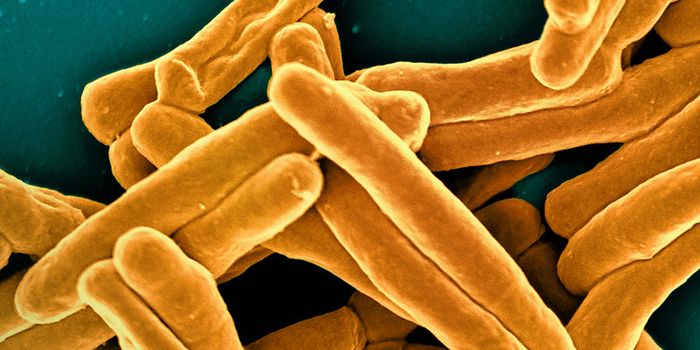

SEP 05, 2024Cell & Molecular BiologyCorynebacterium matruchotii ia a common bacterium that lives in human dental plaque; a colony is seen in this image by S ...